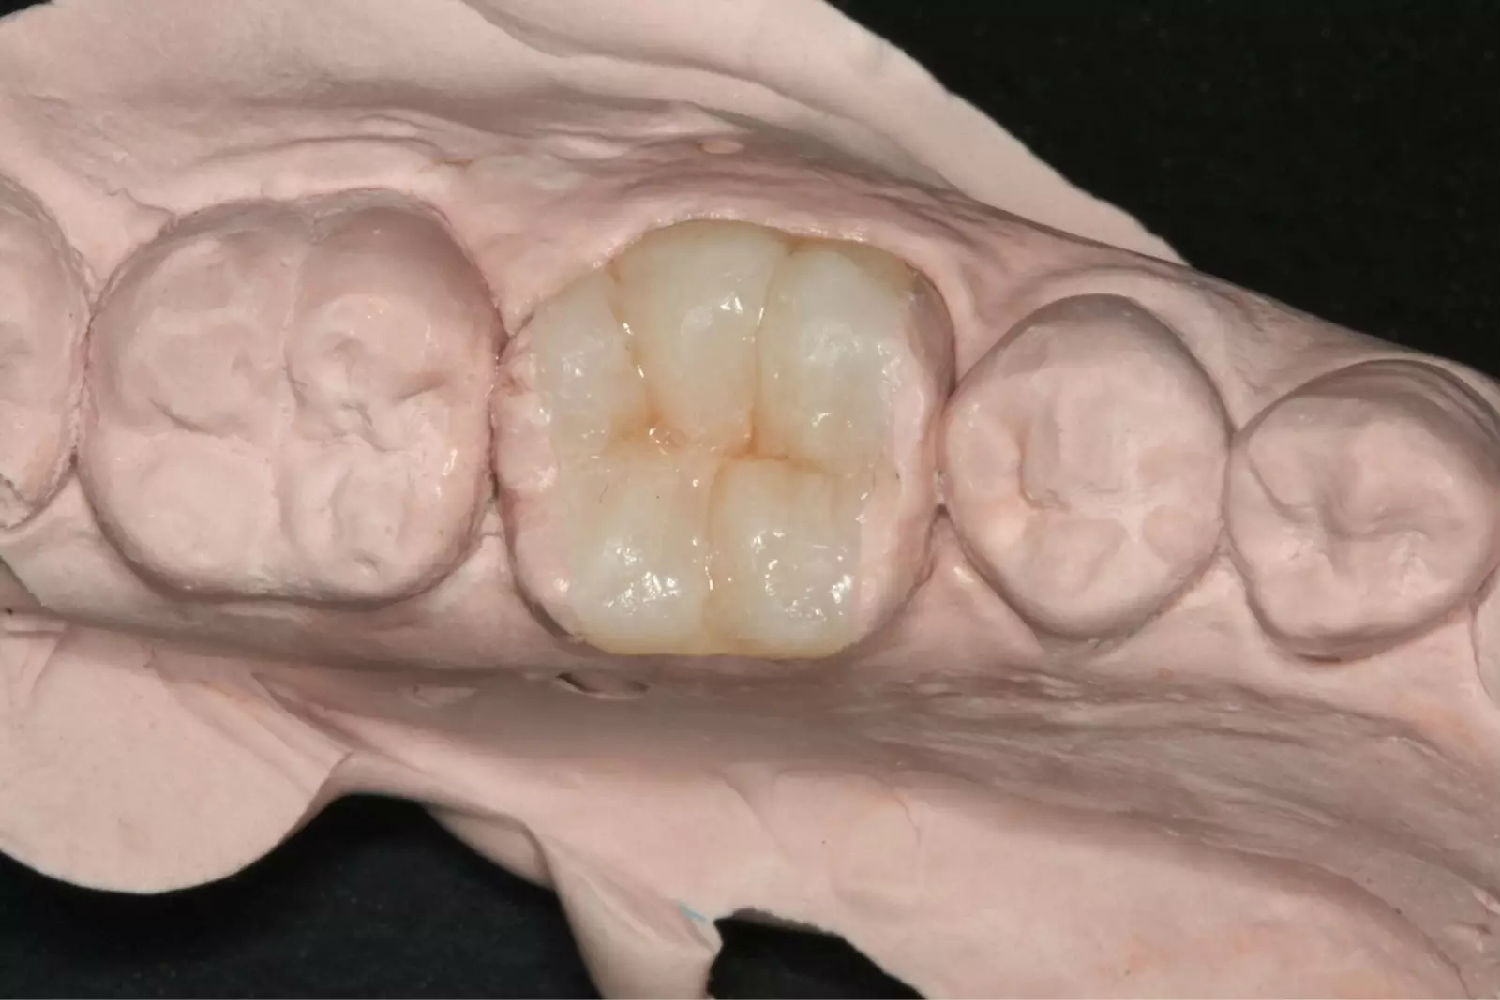

另附一例上腭多行性腺瘤一例。